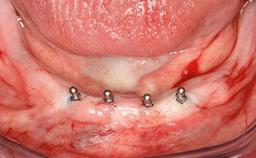

Mandibular Overdenture Supported by a CAD/CAM-milled Bar with Long Distal Extensions on Two Conventionally Loaded Implants

# of Implants 2

Type of Implants One-Piece

Modality 2 interforaminal implants